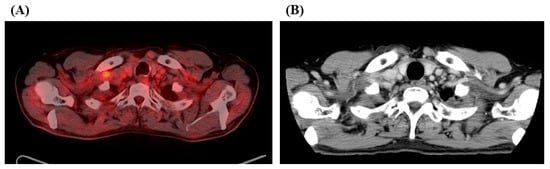

2. Case Report